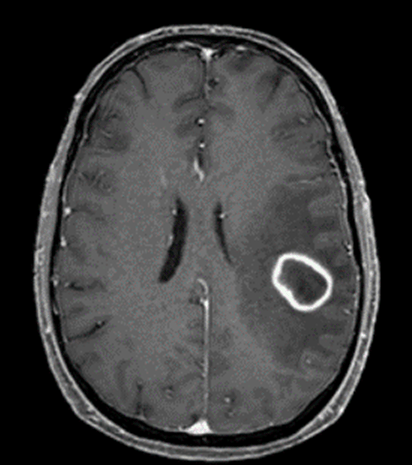

A 55 year old male with a 43-pack-year smoking history was transferred to our hospital for evaluation of new onset neurologic deficits including slurred speech, aphasia, and right upper extremity diminished dexterity and neglect. CT chest was remarkable for a mass in the superior segment of the left lower lobe. Needle core biopsy of the lung mass revealed poorly differentiated non-small cell carcinoma. Head MRI demonstrated an enhancing mass in the left frontoparietal junction that was concerning for metastasis from a lung primary. The patient was started on chemotherapy as an outpatient. Follow-up imaging showed growth of the brain mass. A biopsy of the brain mass showed no evidence of metastasis, only “reactive brain with foci of dense mixed inflammation and filamentous bacteria consistent with abscess.”

Central nervous system nocardiosis may occur in any region in the brain and can present with mass effect symptoms without typical infectious symptoms, as in our patient. Prognosis varies based on the extent of disease and the cause of a patient’s immunosuppression. Treatment of CNS nocardiosis usually begins with an induction phase of intravenous TMP-SMX and imipenem for 3-6 weeks or until there is clinical improvement. Once the patient improves, they can be switched to oral therapy with a sulfonamide and/or minocycline and/or amoxicillin-clavulanate.